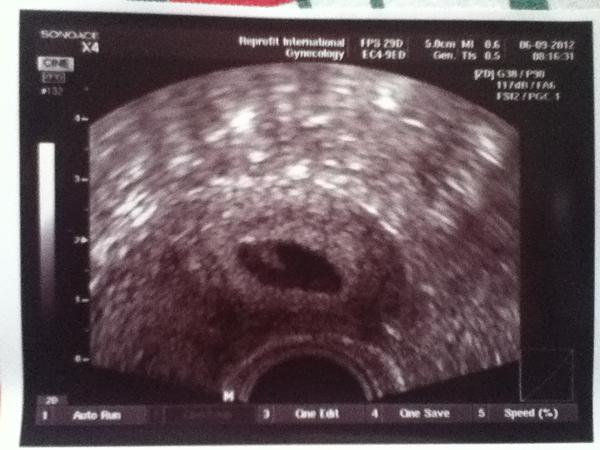

@drndapetka Ahojky tak jsem zpět..🙂 Kuřecová tam sice nebyla, ale to neva..I Vitoušková mi dnes udělal radost..🙂 Takže srdíčko máme a odpovídá 6+3 tak o den míň než podle MS..🙂 Mám obrouvskou radost...🙂 A pošílám foto našeho miláčka

A díky všem holky za držení palců, pěstí prostě všeho..🙂